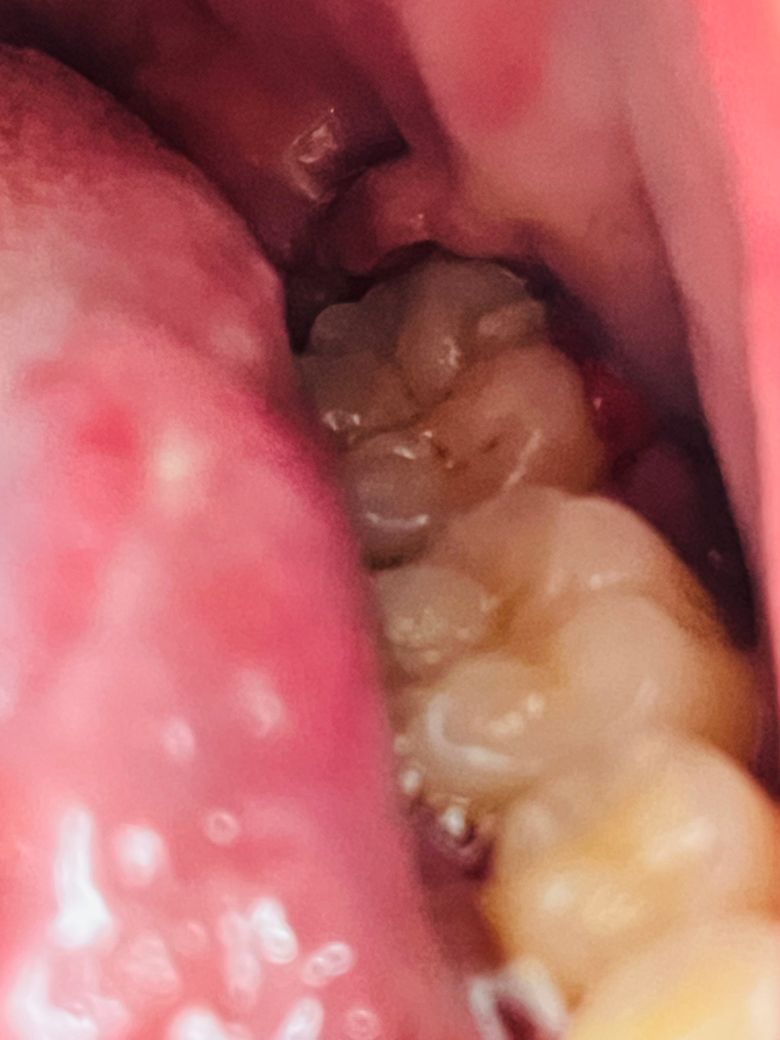

매복 사랑니 발치했는데 잘 회복되고 있는건가요?

위 사진처럼 무슨 이상한 덩어리가 볼록튀어나와잇어서 머 씹을때도 아프고 ㅠ 통증은 덜한데 먼가 잘 회복되규 있는지 의문이라서요

마치 꼬맨거 때문에 꽉 조여져 있어서 저렇게 된 것 같기두하구...정상적인 상황인건가요?

사진상으로 보면 잘 아물고 있는거 같습니다. 아직은 잇몸이 다 아물지 않아서 그쪽으로 식사를 하시면안됩니다.

붓기가 심하고 조직을 꼬맨 것으로 인해서 그런 것으로 보이며 특별히 문제가 보이지는 않습니다.

사진으로 봤을 경우에는 크게 문제가 되지 않을것으로 생각됩니다.

특별히 사진 상 치유지연되거나 하는 양상은 안보입니다만 볼과 주변 잇몸을 씹어서 약간 부어있긴 합니다. 해당 부위를 피해서 음식 드시기 바랍니다.